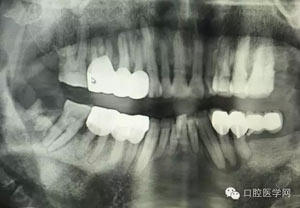

病例1:患者迫切希望保留自己的這一顆牙齒,根尖周陰影比較大,二度松動(dòng).而且旁邊有種植修復(fù)體,和患者溝通好后,治療好后觀察一個(gè)月后冠修復(fù),因?yàn)橛蟹N植的后期修復(fù),所以有了機(jī)會(huì)觀察,術(shù)后三個(gè)月和術(shù)后四個(gè)月,根尖恢復(fù)的還算不錯(cuò),希望能夠繼續(xù)觀察下去.這樣子的病例,做的時(shí)候我們一定要非常的小心,和患者要有充分的溝通以及不同科室的溝通然后決定怎么樣做比較好,假如就是出現(xiàn)了問(wèn)題,到時(shí)候我們也比較好處理些,免得我們自己到時(shí)候不好收?qǐng)觥?/span>